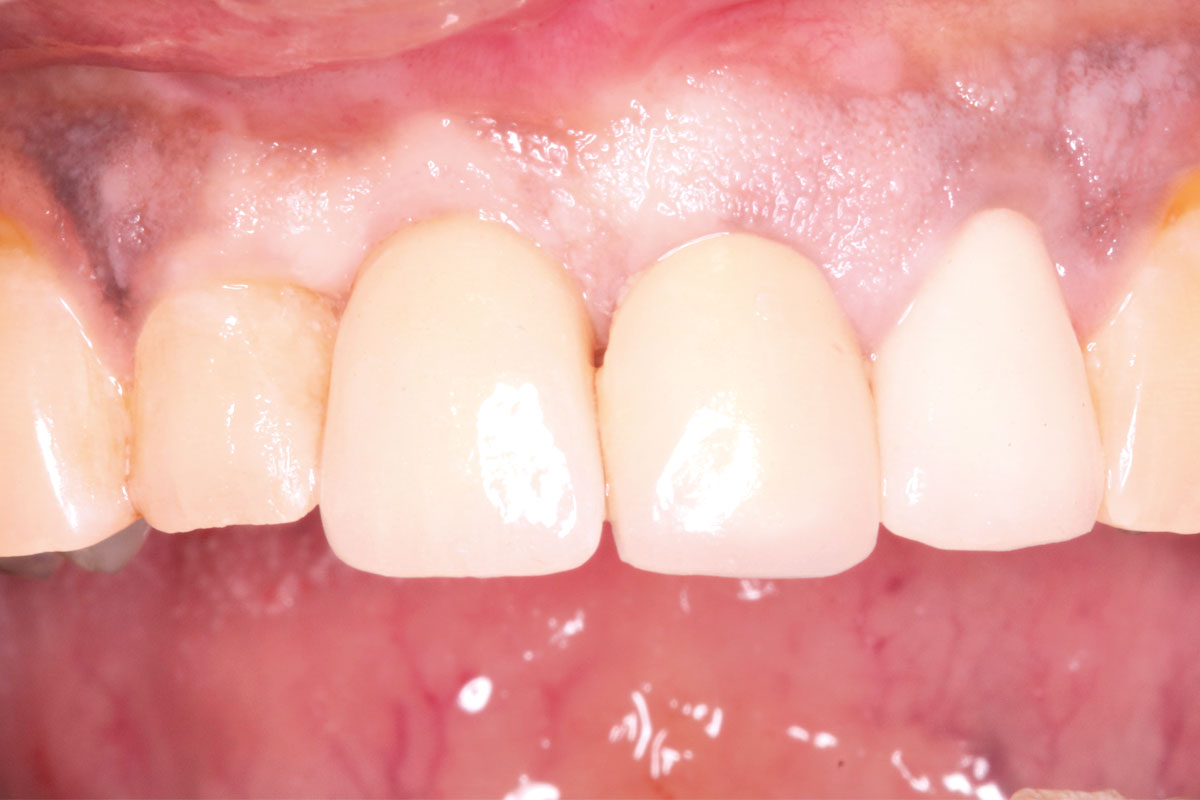

Delayed implant placement with GBR and soft tissue augmentation at the aesthetic area  -  2 years follow up – Dr. H. Maghaireh & Dr. V. Ivancheva